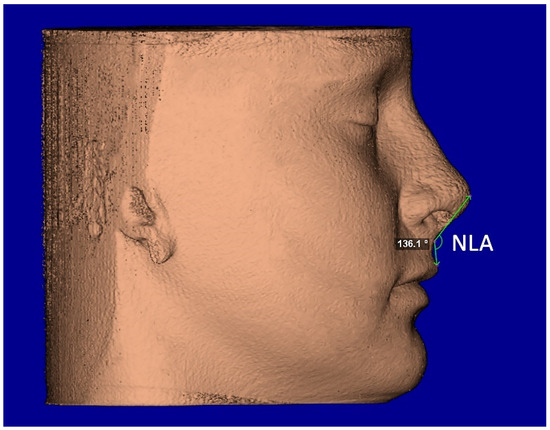

The segmentation mask of facial soft-tissue was created, setting the Hounsfield units threshold between −1024 and −200 and then converted into a 3D rendered model. The analysis of the nasal soft-tissue region was performed using the following measurements [17] (Table 1): Alar base width (ABW) (Figure 5), Alar width (AW) (Figure 5), Length of the nose (NL) (Figure 6), Length of the nasal filter (NFL) (Figure 6), Naso-labial angle (NLA) (Figure 7).

Figure 7.

Facial soft-tissue linear measurement of the naso-labial angle (NLA).

A small increment of nasal length (NL), nasal filter length (NFL), and nasolabial angle (NLA) were found in both groups between T0 and T1; instead, a small reduction in the same measurements was recorded at T2. However, these changes were not statistically significant (p > 0.05) (Table 3). Finally, no differences were found between the TB and BB groups in the changes of NL, NFL, and NLA recorded at 6 months (T0–T1) and 1 year (T0–T2) after maxillary expansion (p > 0.05) (Table 4).

4.2. Post-Retention Sagittal Changes

Another assumption of this study is the possibility that RME, in the form of TB and/or BB anchorage, can change the sagittal projection of the soft tissue in the nasal region. A small increment of nasio-labial angle, nasal filter, and nasal length was found in both TB and BB groups; however, these findings were not statistically significant as well as they did not differ between the two groups. As far as we know, the only study that looked at the height of soft tissue in the nose was that of Magnonson et al. [18]. In that study, the authors found an insignificant increase (p > 0.05) of 0.18 mm, but in contrast to our study that observed changes after RME, they were observing changes following surgical disjunction. Nevertheless, despite being not statistically significant, the increment of nasio-labial angle, nasal filter, and nasal length data were consistent and could be attributed to adaptive postural changes to accommodate the width and thickness of the expander appliance [24].